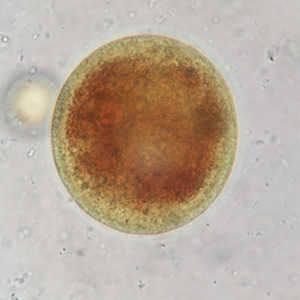

Le kyste est sphérique à ovoïde, à paroi épaisse, mesurant 50 à 100 μm de diamètre. Il présente un contenu granuleux, un macronucléus et micronucléus difficilement visibles (Strait et al., 2012). La coloration au Lugol permet de mettre en évidence certains organites qui apparaissent en brun sombre, de colorer la paroi en brun et l’intérieur du kyste en jaune.